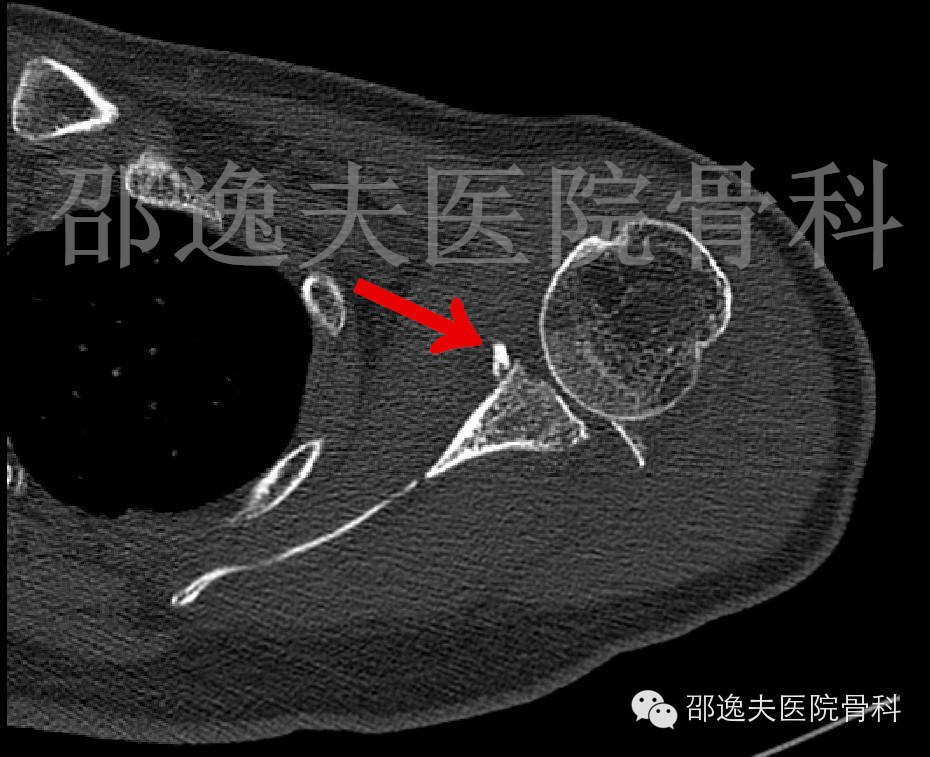

肩部CT扫描

这是典型的骨性Bankart损伤,即指外伤导致肩关节前脱位后与肩关节盂前下缘撞击发生的关节盂前缘撕脱骨折。

术后复查右肩关节CT扫描

检查显示位置良好、固定确实可靠。